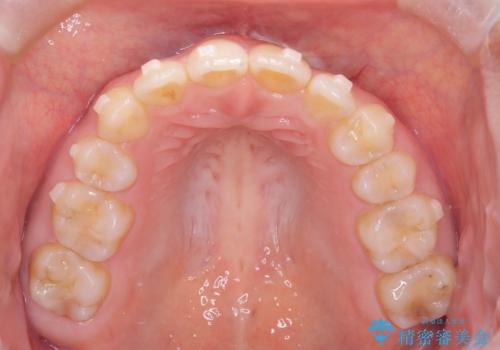

矯正後の後戻り インビザラインで改善

- 7ヶ月

- 前歯のガタツキが気になると来院されました。

マウスピース矯正治療を選択しました。